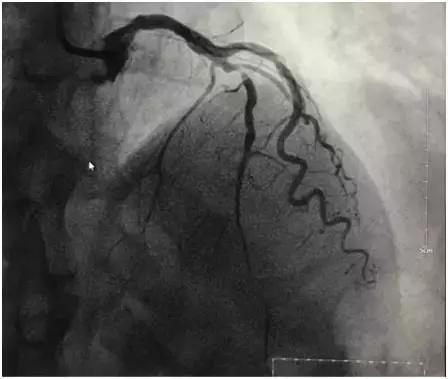

病例1,李大爷今年64岁,平素身体健康,无高血压、糖尿病等病史,平素无吸烟史,由于生在农村,无论严寒酷暑,农活从未停息过,自觉身体很棒,随时笑口常开。近三四天自觉很疲乏,间感胸口隐隐疼痛,轻微活动即感胸痛明显加重,李大爷自认为“感冒”,卧床休息两天或服用点感冒药即可好转,可连续休息两天无好转迹象,入院前一晚(12月6日)夜间4点胸痛症状明显加重,持续不缓解,伴大汗淋漓,呼吸困难。立即送入当地医院,考虑“心梗”,于次日12时转至我院急诊科,我科会诊后诊断“急性心肌梗死”,考虑仍在急诊PCI治疗的时间窗内,立即启动导管室,通过绿色通道,急诊进行冠脉介入。造影显示左前降支近段99%狭窄,次全闭塞。随后予球囊扩张狭窄处,置入支架一枚,血流立即通畅,李大爷胸痛顿时明显缓解,生命体征平稳,转入监护室继续治疗。

左冠脉造影:前降支中段99%狭窄